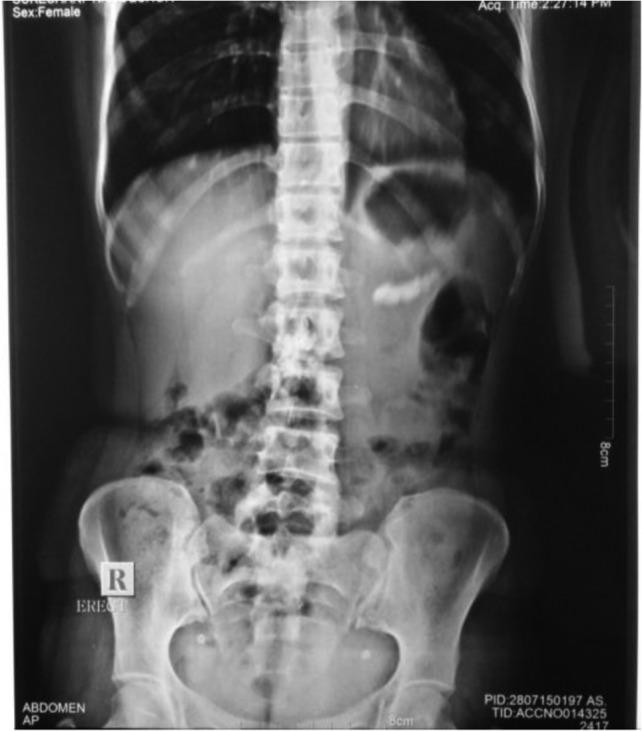

Acute obstructive suppurative pancreatic ductitis (AOSPD) is a rare complication of chronic pancreatitis that has been described in only seven previous case reports since 1995. We report a case of a 33-year-old female a known case of chronic pancreatitis with computed tomography suggestive of dilated main pancreatic duct with multiple calcifications. On exploration, pancreatic duct aspiration revealed frank pus. Pus was drained after opening the pancreatic duct and longitudinal pancreaticojejunostomy was done. Patient was relieved of her symptoms after surgery. In conclusion, AOSPD should be considered in long standing cases of chronic pancreatitis. AOSPD appears to respond quickly after drainage procedure like longitudinal pancreaticojejunostomy and should be considered the treatment of choice.

急性梗阻性化脓性胰管炎(AOSPD)是慢性胰腺炎的一种罕见并发症,自1995年以来仅有7例先前的病例报告对此进行过描述。我们报告一例33岁女性病例,该患者为已知的慢性胰腺炎患者,计算机断层扫描显示主胰管扩张并伴有多处钙化。术中探查时,胰管抽吸发现有脓性液体。打开胰管后引流出脓液,并进行了纵行胰管空肠吻合术。患者术后症状缓解。总之,对于长期存在的慢性胰腺炎病例应考虑AOSPD。AOSPD在纵行胰管空肠吻合术等引流手术后似乎反应迅速,应被视为首选治疗方法。